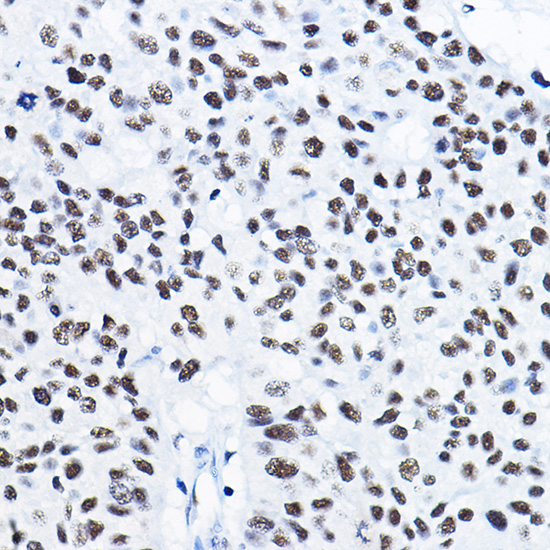

Notch signaling pathway is a highly conserved signaling pathway, which regulates the growth and development of organism via cell to cell interactions. It consists of transmembrane receptors, ligands, the nuclear binding proteins and target genes. Activated by ligands from the neighboring cells, notch receptors regulate proliferation and differentiation of various cells accurately through interaction between a series of molecules. Notch signaling pathway plays an important role in cell fate determination, central nervous system development and function, organ formation and somitogenesis during the development of vertebrate and invertebrate. Aberrant notch signaling pathway is associated with some tumorigenesis, which also plays a different regulative role in proliferation, differentiation, apoptosis and other processes of tumor cells regarding to various tissues or cell stage.